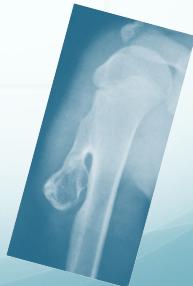

Bone Tumors and Tumor-like Conditions

Malignant Bone Tumors

- Features, bone, site, age, and X-ray shape characteristic for each tumor